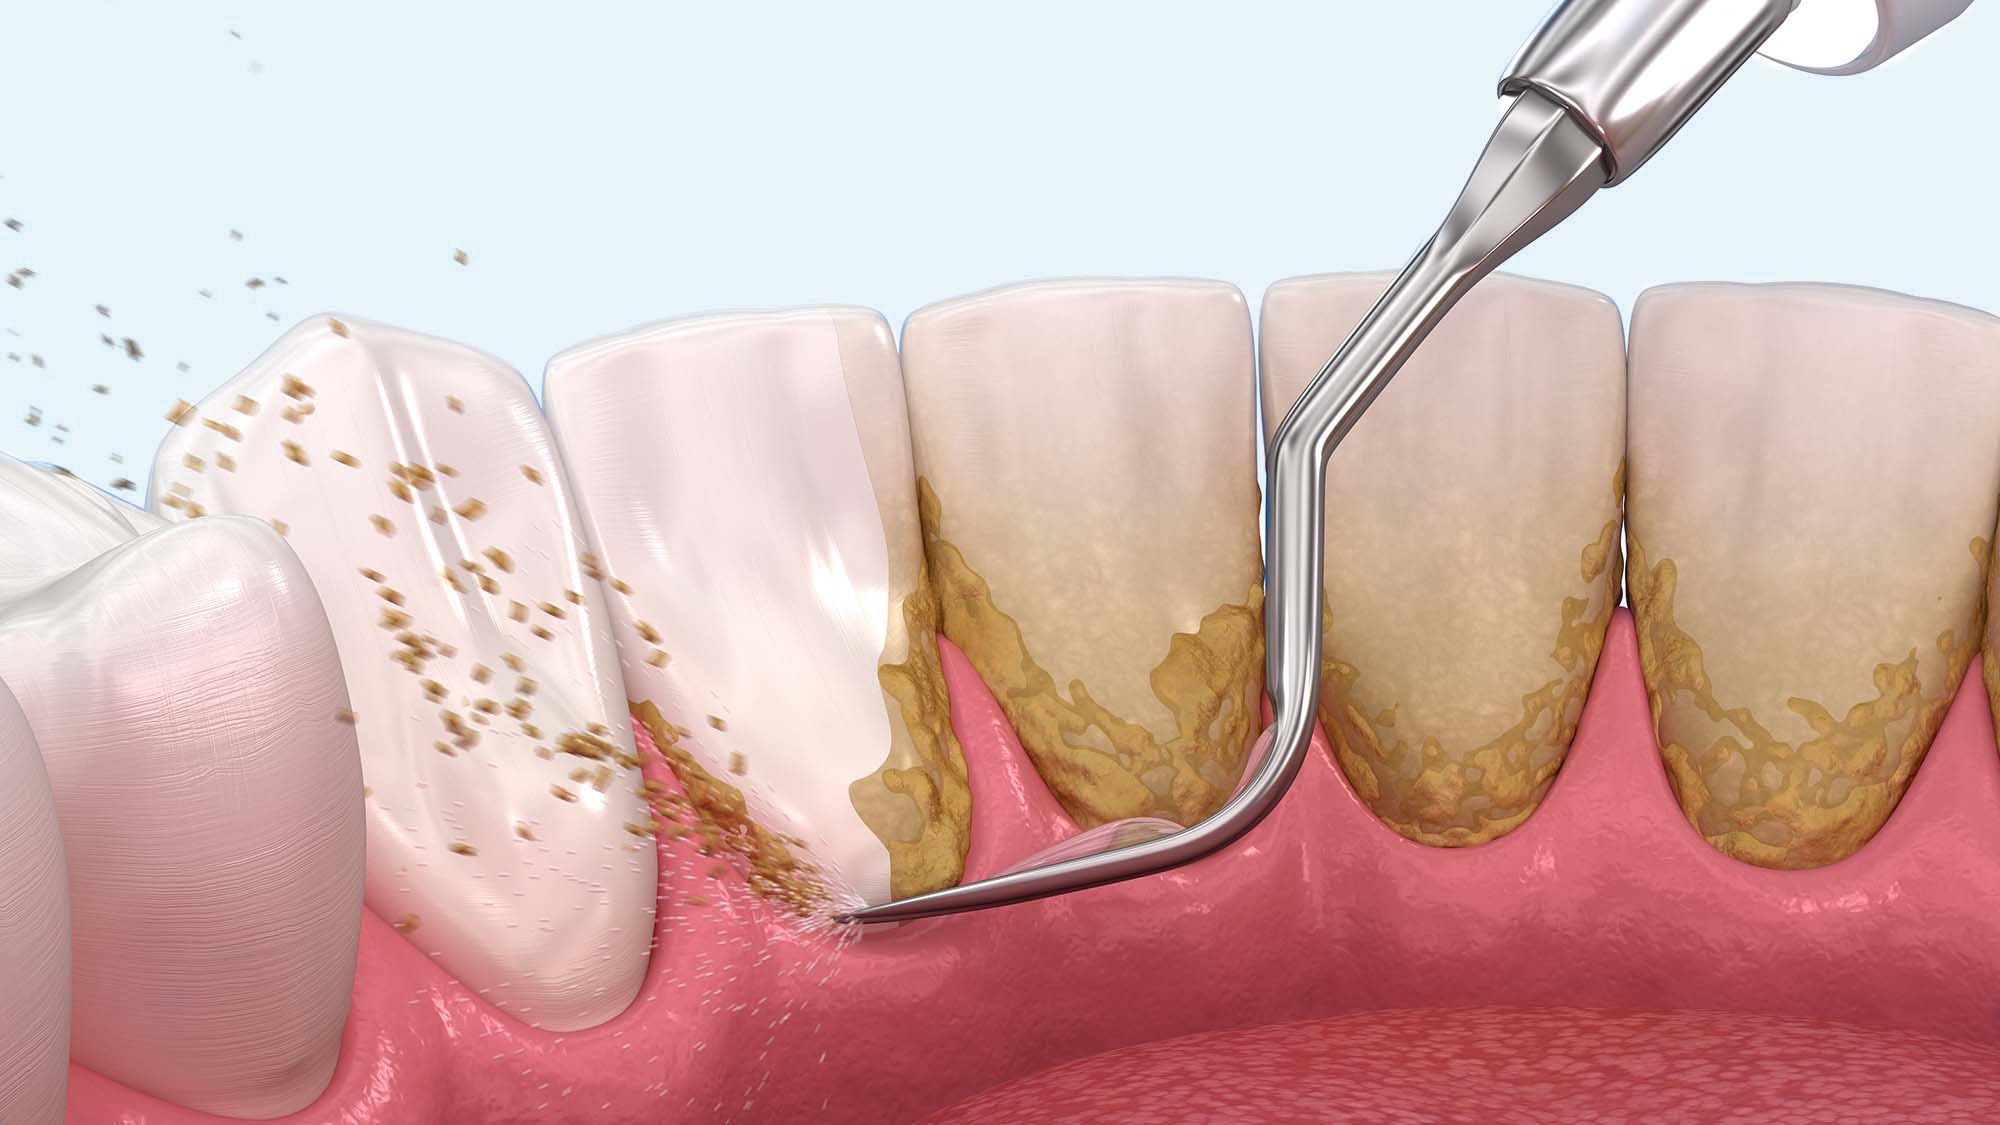

歯石除去(スケーリング)

歯と歯茎の間に溜まった歯石を特殊な器具で除去します。歯肉炎の主な治療法として効果的で、出血や炎症の改善につながります

03専門的なお口のクリーニングと歯石除去専用器具で歯石を取り除き、専門的なお口のクリーニング(PMTC)を行い、歯の表面を清掃します